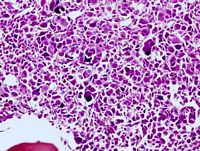

Twelve months later, sternal  osteolysis (Figure 1) and a 6th left rib fracture were identified. Haematological investigation revealed anaemia (8 g/dL), WBC of 20 x 109/L with neutrophilia and Plt of 150 x 109/L. Rib and sternal biopsies (Figures 2 and 3) revealed the diagnosis of acute megakaryoblastic leukemia (AML7). Cells expressed: CD34, CD31, EMA (epithelial membrane antigen), lysozym, factor VIII and MPO. They were negative for: CD3, CD5, CD20, CD73a, CD56, CD68, and CD15AB antigens. Karyotype remained normal.

Figure 2. Bone marrow biopsy showing imature cells of variable size and some bone marrow fibrosis (at x 20 magnification)

Figure 3. Biopsy of  lesion on the sternum showing dystrophic megakaryocytes (at x 20 magnification)